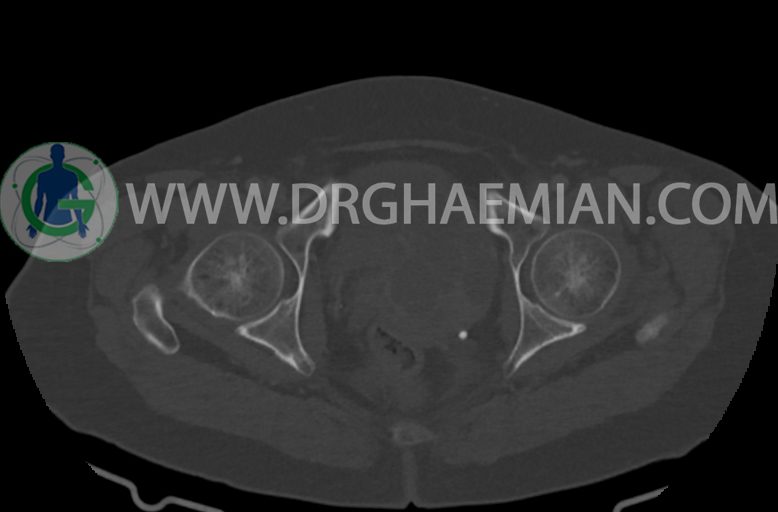

–ساختار Cystic multiseptate همراه با Enhancing thick septation به ابعاد 79x62mm در

لگن دیده می شود که در درجه اول مطرح کننده ی ضایعات نئوپلاستیک تخمدانی نظیر mucinous cyst adenocarcinoma است.

–شواهد هیسترکتومی

–ضایعه ی mass like هیپردنس- هتروژن به قطر 42mm در سمت راست لگن